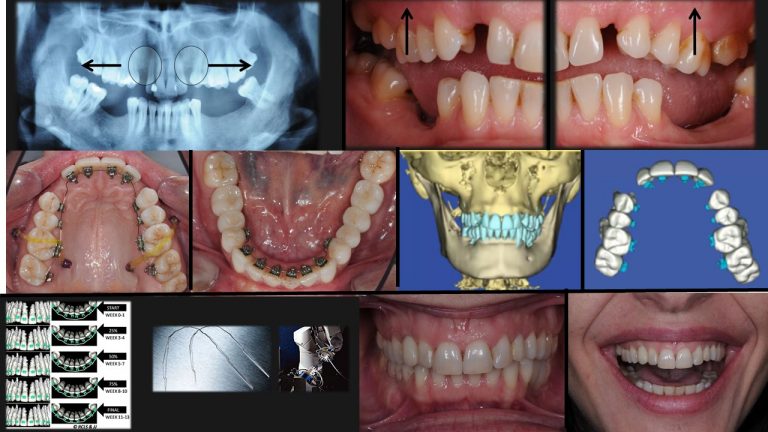

תכנון תלת ממדי של הטיפול האורתודונטי

Suresmile

שורסמייל, השיטה היחידה בה יש לאורתודונט יכולת לשלוט ולתכנן את כל התנועות האורתודונטיות בצורה מדויקת באמצעות כל סמך שהוא בוחר ובכל גישה, (סמכים חיצוניים או סמכים פנימיים או שילוב בין שיטות טיפול).

שורסמייל היא הטכנולוגיה המתקדמת ביותר שישנה כיום בעולם לתכנון מדויק ולהשגת תוצאות אופטמאליות בטיפול האורתודונטי.

שיטה זו פועלת כעשור בארה"ב.